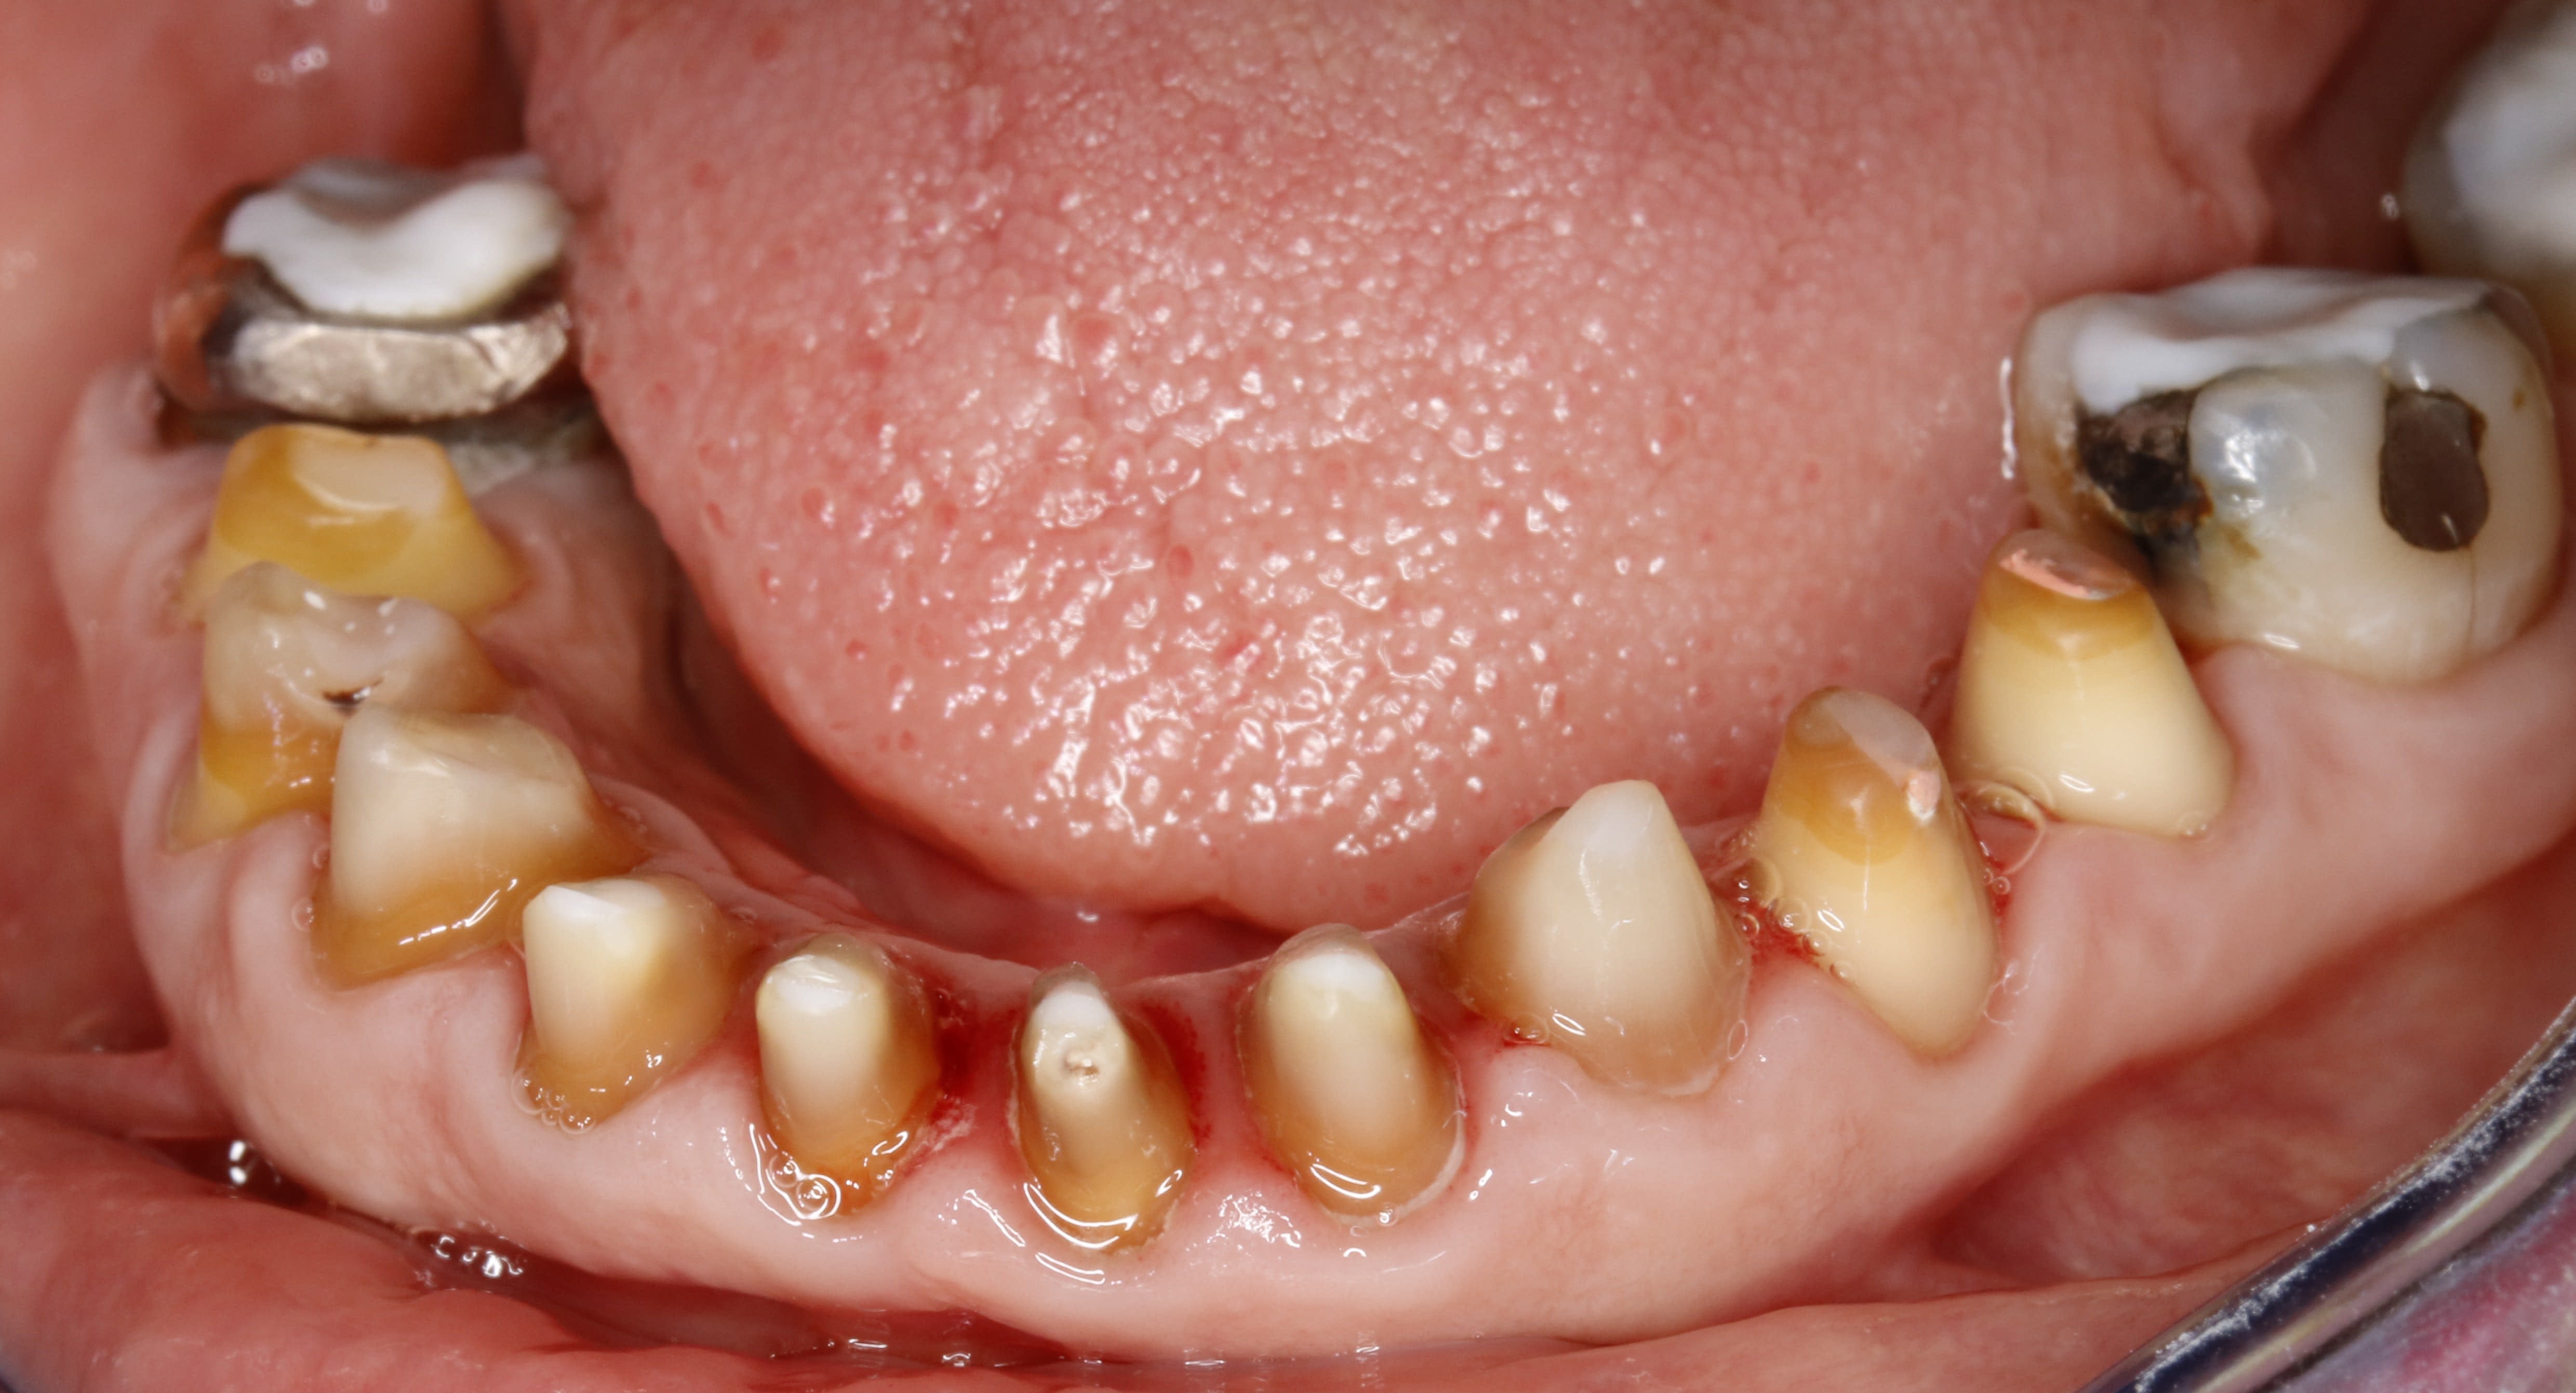

bridge du bas vue occlusale

mg 1948 ey7kzp - Eugenol